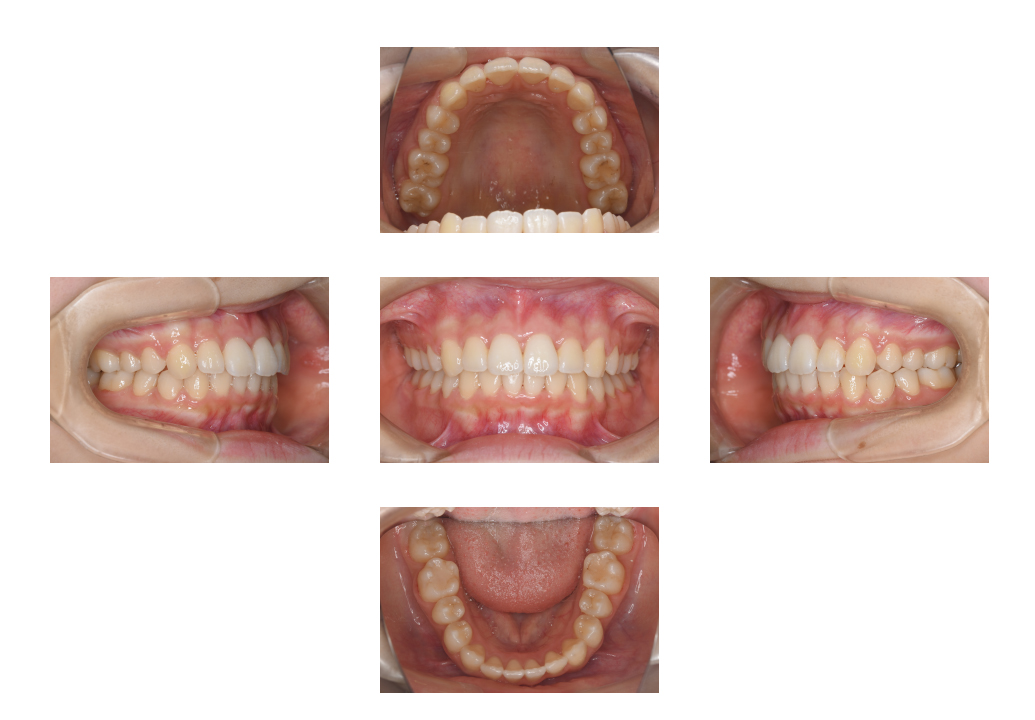

10代 歯並びが気になる

Before

After

通院時の年齢 10代 性別 男性 通院目的 歯並びが気になる 処置内容 ・非抜歯治療

・ハーフリンガル装置にて治療通院回数 1年3カ月(16回) 費用 ・ハーフリンガル装置 770,000+税

・ホワイトワイヤー使用

処置料7,150円×16回の来院リスク・副作用 自由診療になるため、虫歯治療などの保険診療と比べ治療費が高額になり治療期間も症状によりますが長くなります。